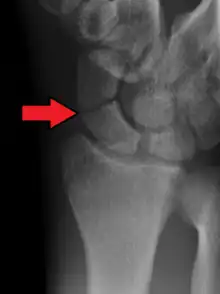

A more obvious scaphoid fracture on a scaphoid view X ray

Scaphoid fractures are often diagnosed using plain radiographs and multiple views are obtained as standard.[9] However, not all fractures are apparent initially.[7] In 1/4 of cases, the clinical examination suggests a fracture, but the X-ray does not show it, even though there is indeed a fracture.[10] Therefore, people with tenderness over the scaphoid (those who exhibit pain to pressure in the anatomic snuff box ) are often splinted in a thumb spica for 7–10 days at which point a second set of X-rays is taken.[7] If a minimally displaced fracture was present initially, healing will now be apparent. Even then a fracture may not be apparent. A CT Scan can then be used to evaluate the scaphoid with greater resolution. The use of MRI, if available, is preferred over CT and can give one an immediate diagnosis.[11] Bone scintigraphy is also an effective method for diagnosis fracture which do not appear on Xray.[12]